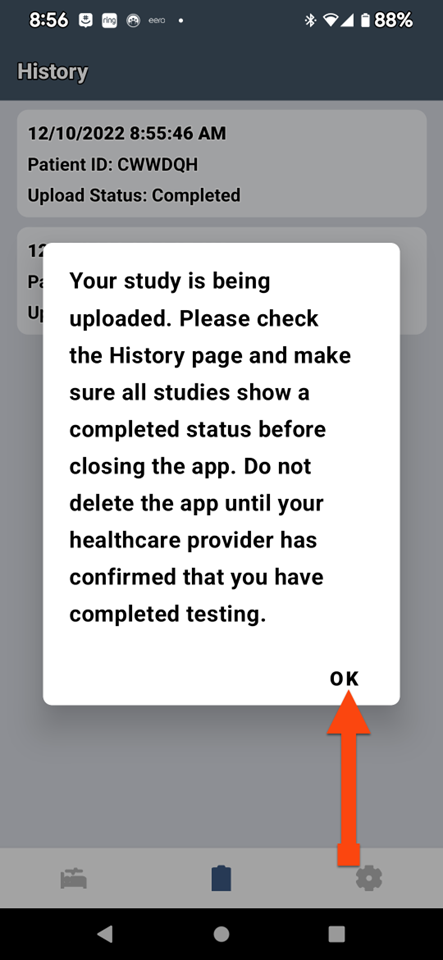

SLEEPIMAGE APP (Android)

SLEEPIMAGE APP (Android)

SLEEPIMAGE APP (Android)

SLEEPIMAGE APP (Android)

SLEEPIMAGE APP (Android)

SLEEPIMAGE APP (Android)

SLEEPIMAGE APP (Android)

SLEEPIMAGE APP (Android)

SLEEPIMAGE APP (Android)

SLEEPIMAGE APP (Android)

SLEEPIMAGE APP (Android)

SLEEPIMAGE APP (Android)

SLEEPIMAGE APP (Android)

SLEEPIMAGE APP (Android)

SLEEPIMAGE APP (Android)

SLEEPIMAGE APP (Android)

SLEEPIMAGE APP (Android)

SLEEPIMAGE APP (Android)

SLEEPIMAGE APP (Android)

SLEEPIMAGE APP (Android)

SLEEPIMAGE APP (iPhone)

SLEEPIMAGE APP (Android)

SLEEPIMAGE APP (Android)

SLEEPIMAGE APP (Android)

SLEEPIMAGE APP (Android)

SLEEPIMAGE APP (Android)

SLEEPIMAGE APP (Android)

SLEEPIMAGE APP (Android)

SLEEPIMAGE APP (Android)